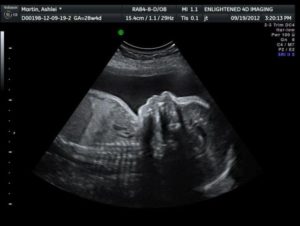

При УЗИ на 28 неделе размер ребёночка от копчика до макушки составляет 20-25 см, к этому времени ножки значительно удлиняются и составляют 10 см, то есть общий рост малыша достигает 30-35 см.

УЗИ на 28 неделе, как правило, назначается для определения положения плода: головное, поперечное или тазовое. Обычно дети на 28 недели занимают головное положение (однако, если ваш малыш не разместился подобающим образом у него впереди еще 12 недель). При тазовом или поперечном положении женщине чаще всего предлагают кесарево сечение.

На УЗИ на 28 неделе вы можете понаблюдать за тем, как малыш двигается в животике, и как открывает и закрывает глазки. Также можно определить кем будет малыш: левшой или правшой (в зависимости от того большой палец какой руки он сосет). Также врач должен произвести все основные измерения для оценки правильности развития малыша.

Для наглядности предоставляем вам норму размеров плода:

- БПР (бипариетальный размер или расстояние между височными костями) — 6-79мм.

- ЛЗ (лобно-затылочный размер) — 83-99мм.

- ОГ (окружность головки плода) — 245-285 мм.

- ОЖ (окружность живота плода)- 21 -285 мм.

Нормальные показатели для костей плода:

- Бедренная кость 49-57мм,

- Плечевая кость 45-53мм,

- Кости предплечья 39-47мм,

- Кости голени 45-53мм.

Фото плода на 28 неделе УЗИ ребенка на 28 неделе Фото живота матери на 28 неделе